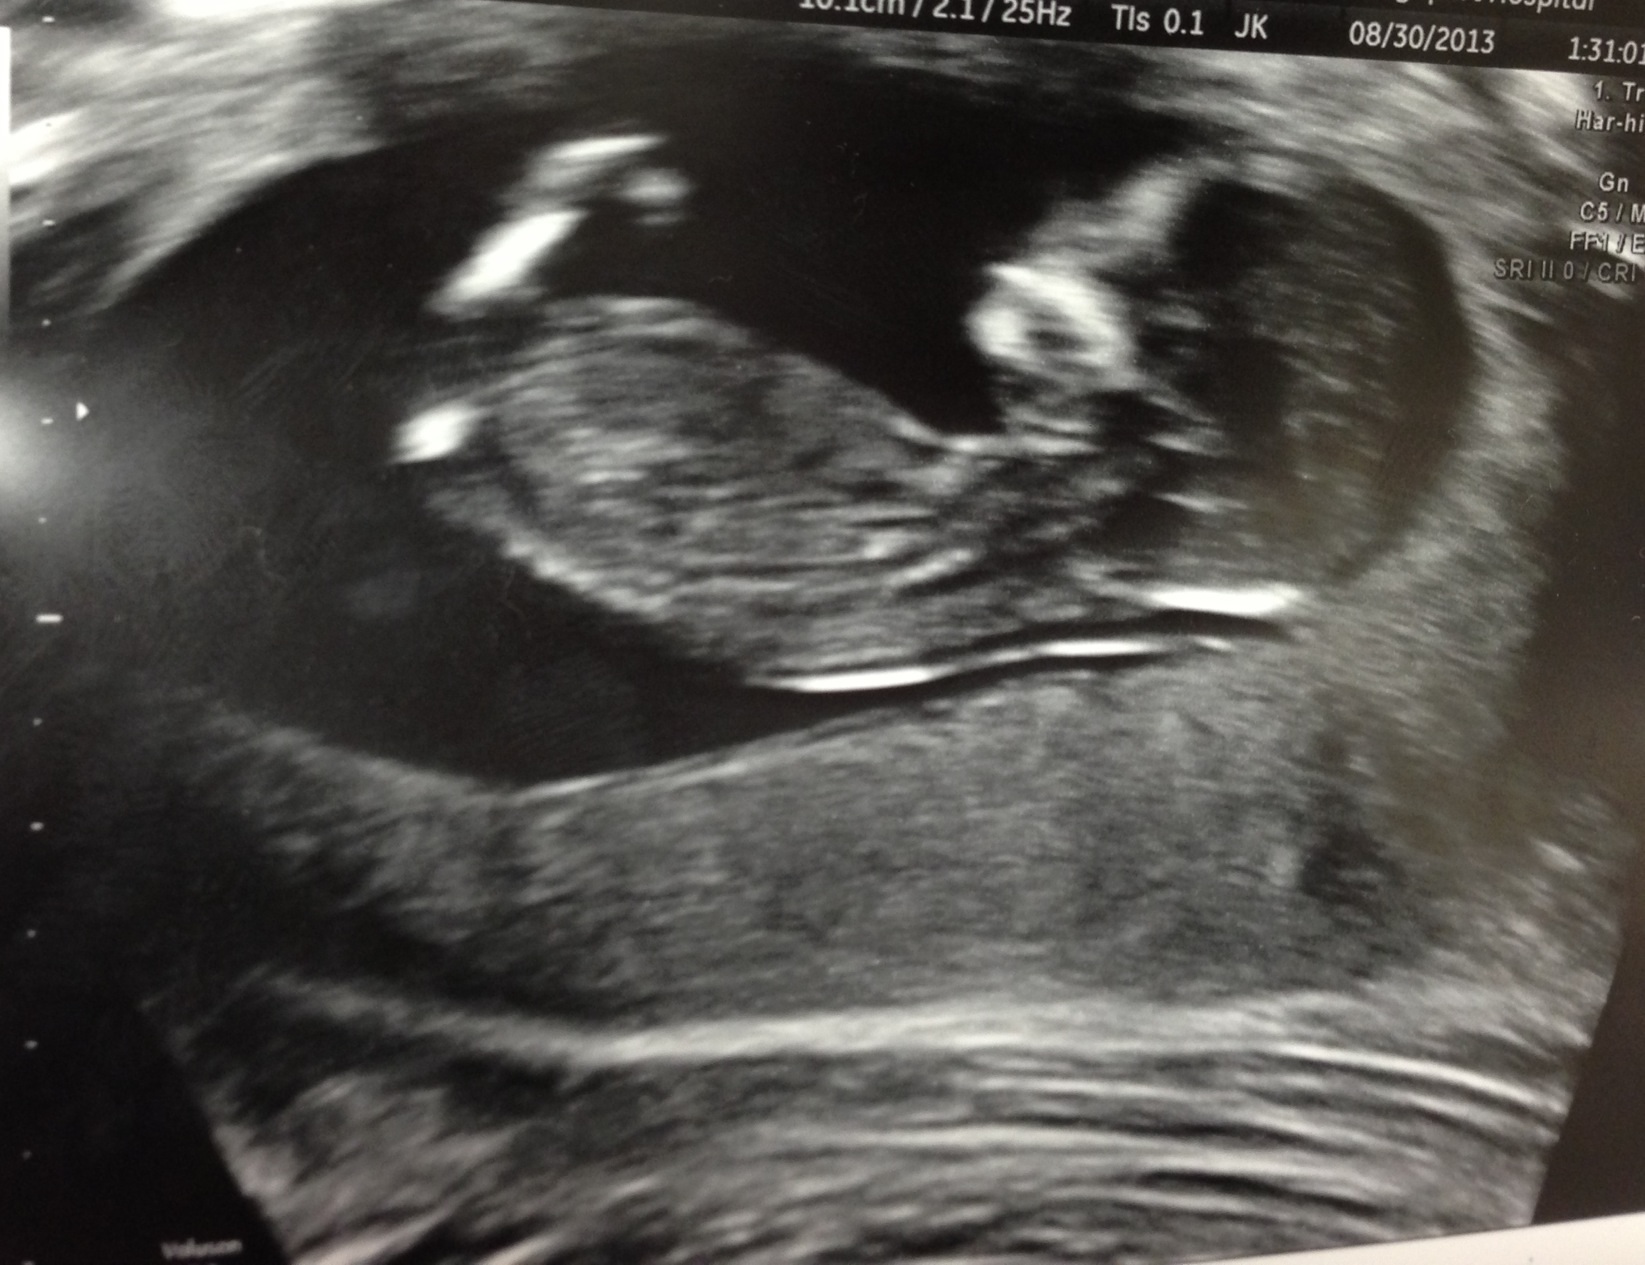

Had our NT scan today. All looked well! Baby measured perfectly at 12w4d and no longer resembles a bean but a tiny little human.

Unfortunately our ultrasound tech couldn't get a good view of "the goods" to give us a gender guess. It was amazing though when she started shaking around to wake baby up to take measurements. Suddenly he/she started turning around and putting its hands on its face. I couldn't believe it! What a great day :)